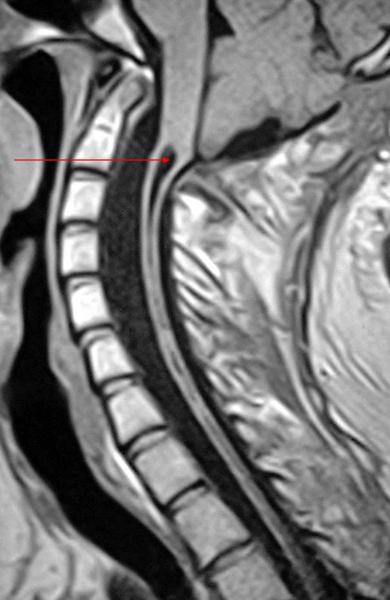

what is syrinx

dilation of the central canal of the spinal cord

what is being pointed out

syrinx